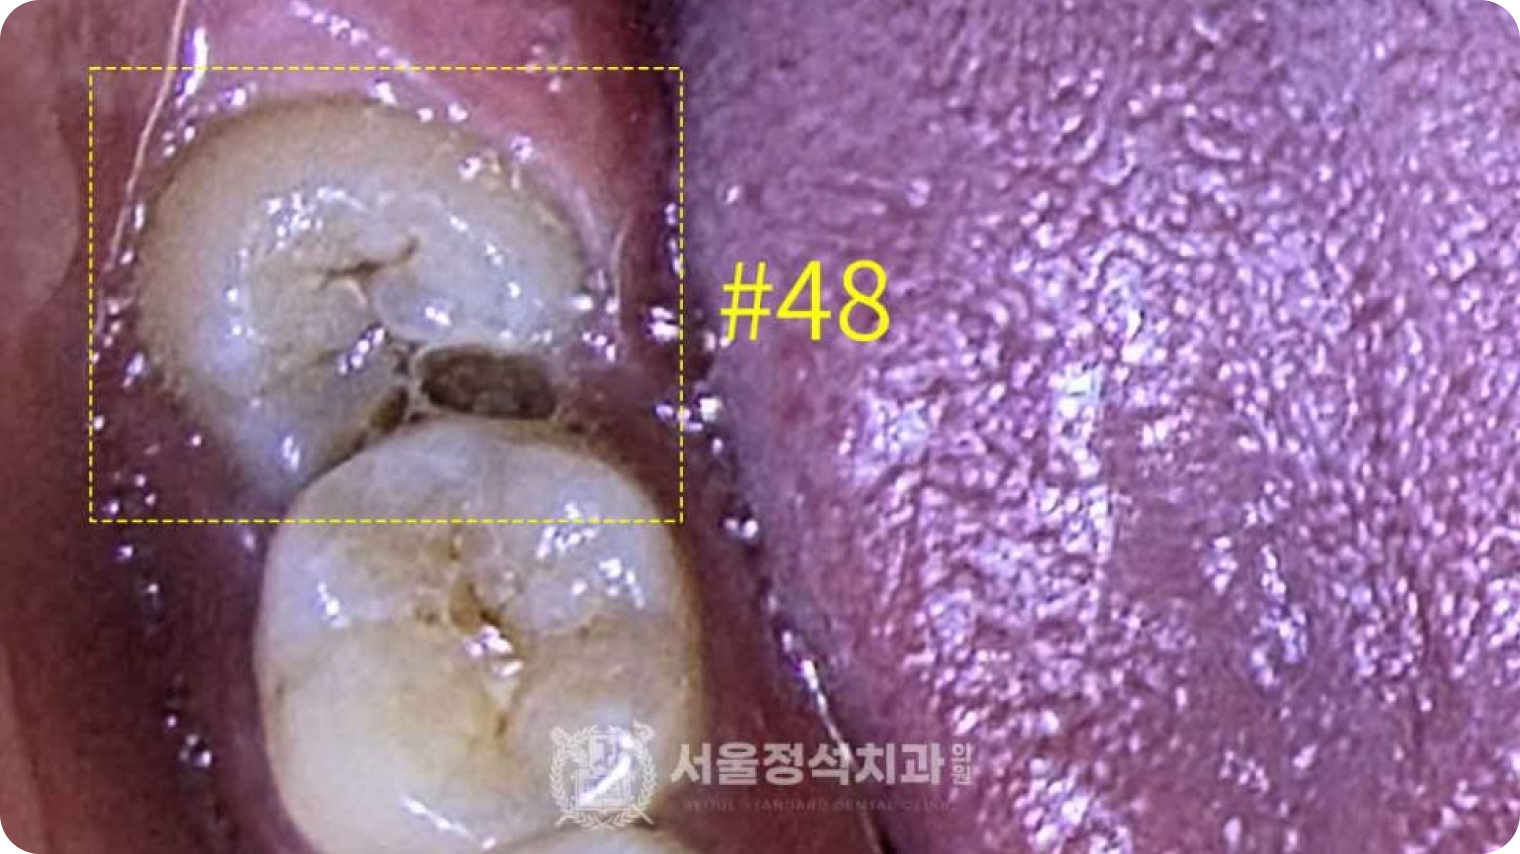

당일 사랑니 발치

당일 사랑니 발치

당일 사랑니 발치

사랑니는 영구치열을 방해하고 관리가 어려워 충치, 염증 등 문제를 일으킵니다. 신경까지 고려하는 당일 사랑니 발치로 빠르고 안전하게 해결합니다.